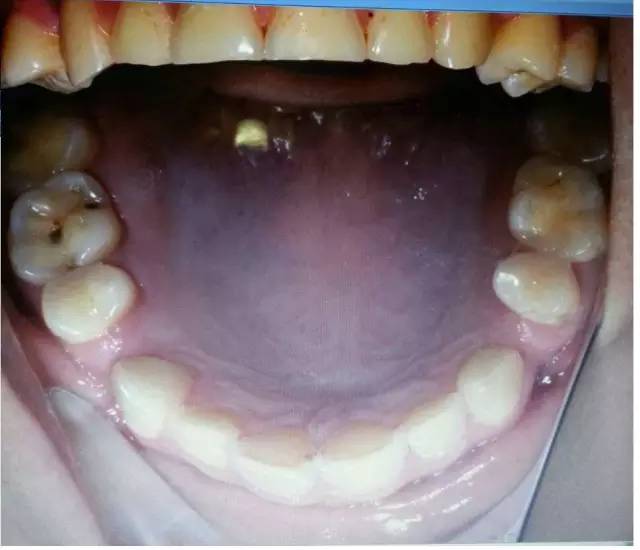

您可能已經(jīng)關(guān)注到患者全口牙磨耗較明顯,請?jiān)囍伎?ldquo;牙齒出現(xiàn)缺損有哪些因素?”

磨耗是超過生理范圍的牙體磨損,是一種病理性磨損,臨床上磨損可并發(fā)各種病癥或?yàn)橹虏∫蛩?,如引起牙本質(zhì)過敏、食物嵌塞、牙髓炎、顳頜關(guān)節(jié)病,以及口內(nèi)軟組織創(chuàng)傷性潰瘍,并可成為致癌的因素

過大的(牙合)力通常是造成磨耗的原因,還有醫(yī)生指出,如患嬰兒式吞咽方式,舌頭在吞咽時(shí)會對牙齒產(chǎn)生推力,導(dǎo)致應(yīng)力集中的頸部出現(xiàn)微折裂也是原因之一。以上幾點(diǎn)都是造成牙體缺損的機(jī)械因素哦!其實(shí)這個(gè)病例給了我們很多信息,需要我們細(xì)致的檢查和問診,來吧,跟著權(quán)老師探究隱藏在表象之下的真相:牙齒出現(xiàn)缺損除了機(jī)械因素,還有什么因素?

是的,牙齒缺損還可能是化學(xué)因素造成的。權(quán)老師追問患者是否有胃病,追問飲食習(xí)慣,果真發(fā)現(xiàn)諸多玄妙之處。“患者喜歡吃酸東西,每頓飯必吃醋,吃完馬上就刷牙。”沒想到吧,這些看似不起眼的飲食習(xí)慣也能探究出與牙齒磨耗的因果關(guān)系,難怪群里郭耀銘老師忍不住感嘆權(quán)老師分享的病例酸味十足哩!這種酸酸的味道是要讓大家學(xué)會分辨機(jī)械因素和化學(xué)因素導(dǎo)致的牙體缺損。